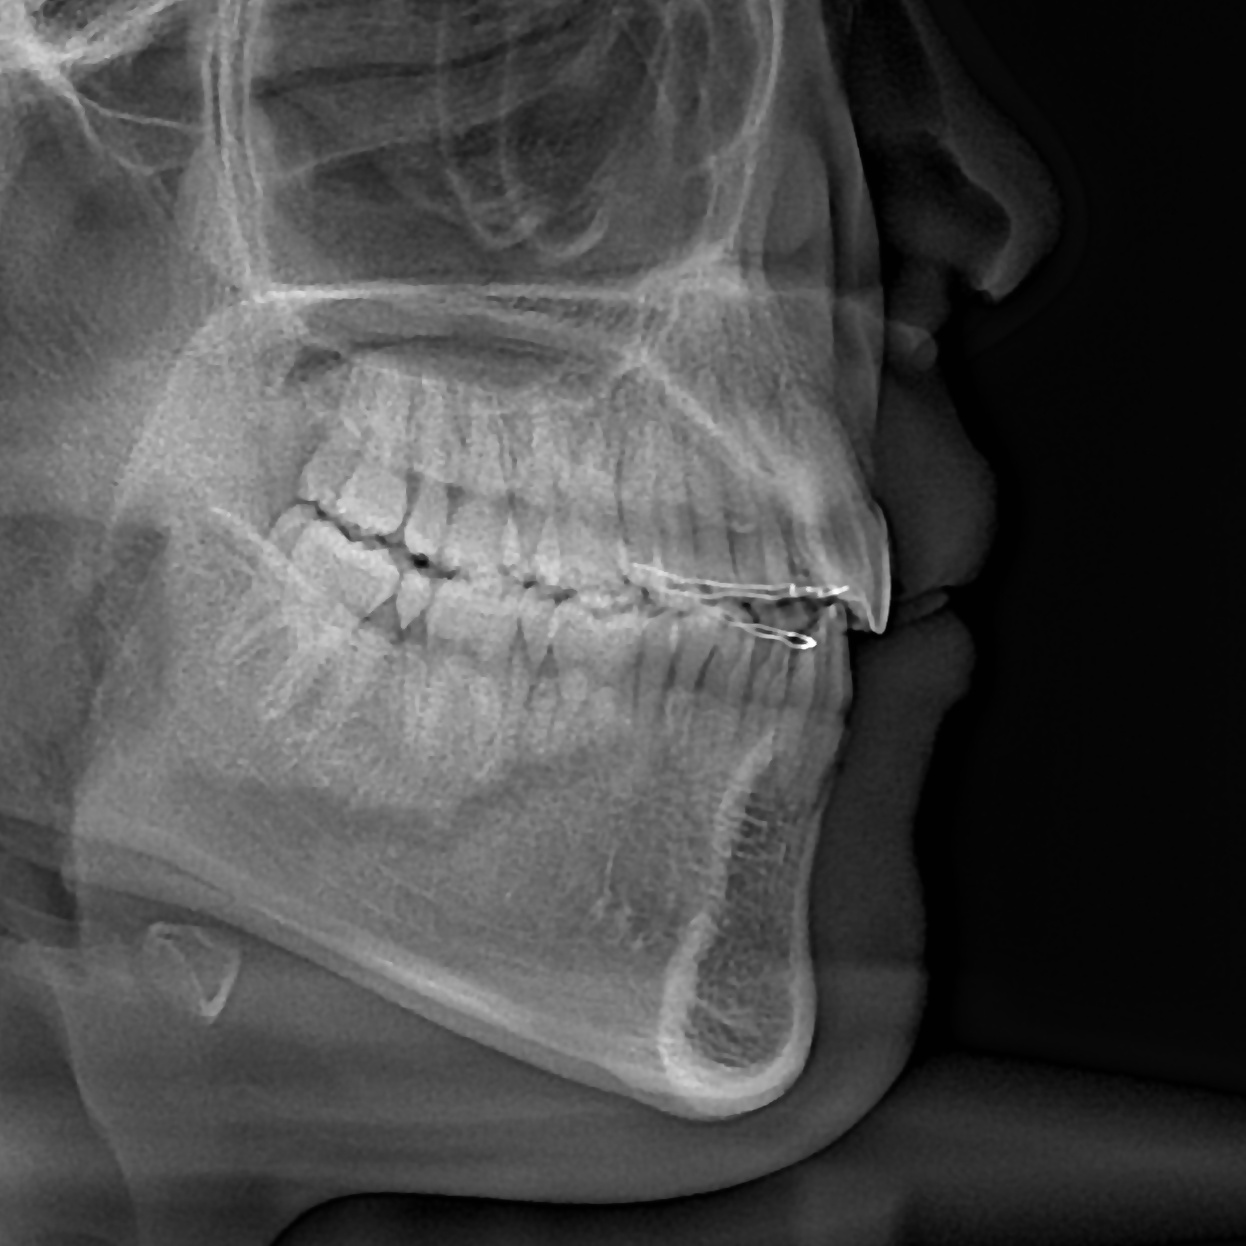

돌출입의 경우 입술의 두께, 앞니의 각도, 후방이동시켜야 하는 양 등을 종합적으로 고려하여 발치 유무를 결정합니다.

위 케이스에서는 발치교정을 이용하여 치아를 후방이동시켜 돌출입을 해소하였습니다.

총 교정기간은 18개월입니다.